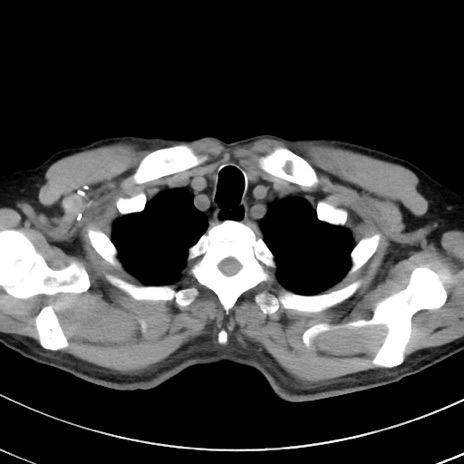

症例38(横断像)

【症例】70歳代 男性

【主訴】腹痛・嘔吐

【現病歴】昨晩より、嘔吐・腹痛あり。今朝になっても嘔吐あり。来院。

【既往歴】心臓バイパス手術、開腹胆摘、腸閉塞

【身体所見】BP 107/71mmHg、HR 116/min、腹部:平坦、軟、下腹部に軽度圧痛あり。反跳痛なし。

【データ】WBC 15100、CRP 0.32